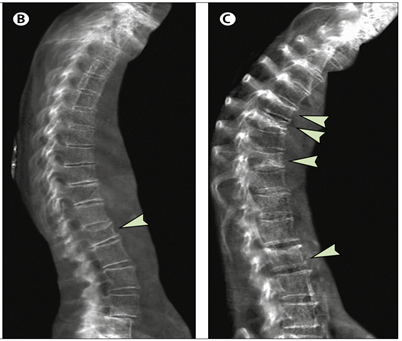

- Gãy cổ xương đùi là một loại gãy xương vùng hông, một biến chứng thường gặp của loãng xương, nó nguy hiểm không kém nhồi máu cơ tim và đột quỵ. Xác suất sống tích lũy sau gãy xương trong 5 năm ở nam và nữ lần lượt là 48% và 59%. Khoảng 1/5 số bệnh nhân bị gãy xương hông tử vong trong vòng 12 tháng [2]

- Gãy đốt sống cũng là một biến chứng phổ biến của loãng xương, tại Việt Nam có 28% phụ nữ loãng xương có biến chứng gãy xương sống [3]. Ngoài tỷ lệ tử vong cao ngoài nó còn gây cơn đau lưng dai dẳng làm ảnh hưởng đến khả năng sinh hoạt và chất lượng cuộc sống.